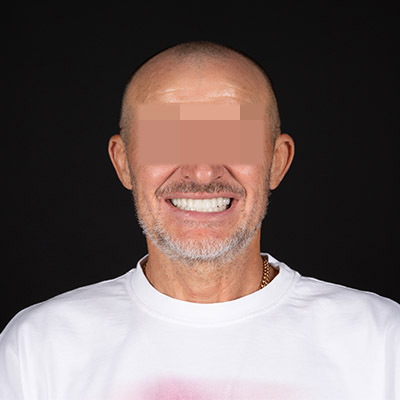

Pacientul și-a dorit să își recâștige zâmbetul pierdut din cauza „parodontozei”.

Am realizat o reabilitare completă cu dantură fixă din zirconiu, pe câte 8 implanturi pe fiecare arcadă, oferindu-i stabilitate și estetică impecabilă.

Rezultatul: un zâmbet natural, puternic și durabil, care îi redă încrederea și confortul de a zâmbi din nou.

înainte

după